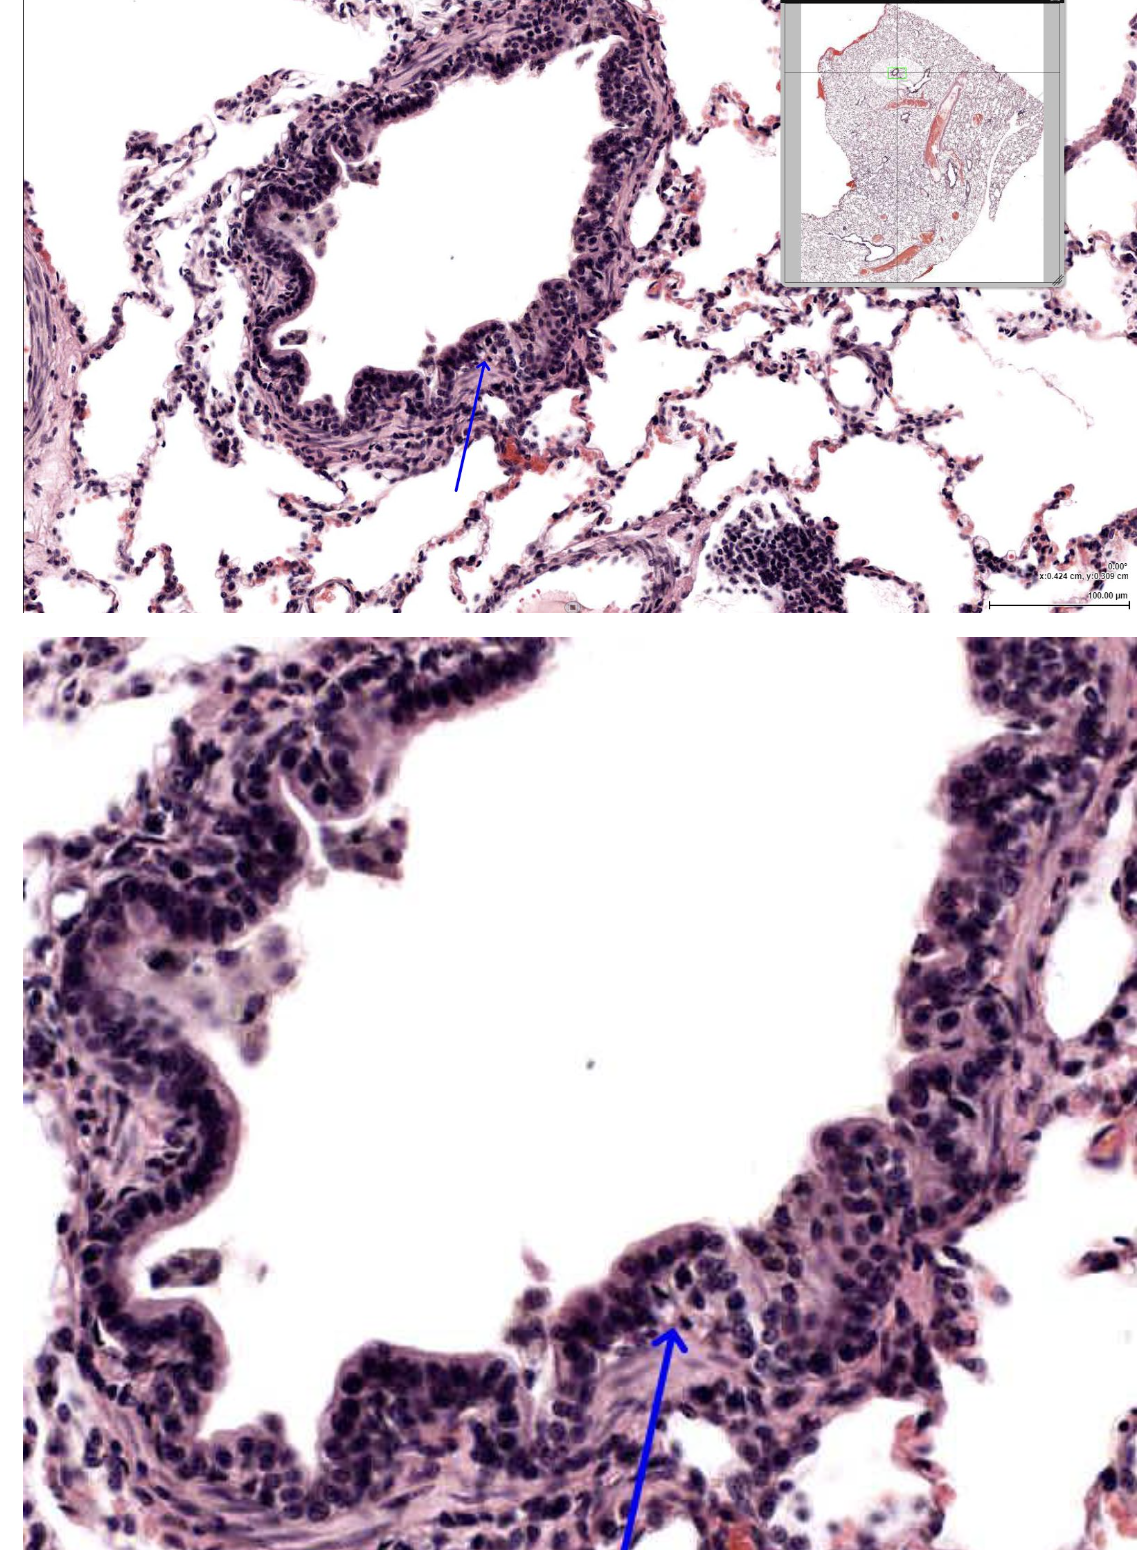

In the attached EM of the blood-air barrier, the structure indicated by the arrow is most likely which of the following?

endothelial cell

In the attached EM of an alveolus, the structure indicated by the arrow is most likely which of the following?

Lamellar body